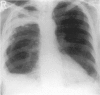

The recurrence rate of spontaneous pneumothorax in patients with underlying lung disease can be as high as 50%. We present a novel method of treatment for recurrent pneumothorax based on the intrathoracic transfer of an extrathoracic muscle flap.

Images in this article